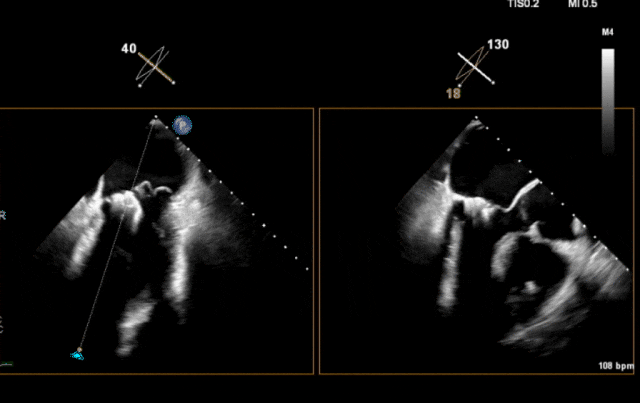

心脏超声示左室增大,二尖瓣2、3区脱垂伴重度反流(腱索断裂),Carpentier分型Ⅱ型,典型Barlow综合征表现;二尖瓣开放面积5.0cm²,3区瓣环内径31mm,前叶长22mm、后叶17mm,前叶收缩期关闭瓣体部分呈拱形突向左房腔,瓣膜游离缘对合欠佳,可见腱索断裂,长度9mm;2区瓣环内径32mm,前叶长22mm、后叶10mm,前后叶均可脱垂;三尖瓣重度反流。CDFI示瓣口重度偏心性反流,反流束沿主动脉后壁走行,肺静脉收缩期可见反向频谱。

术前超声

图片